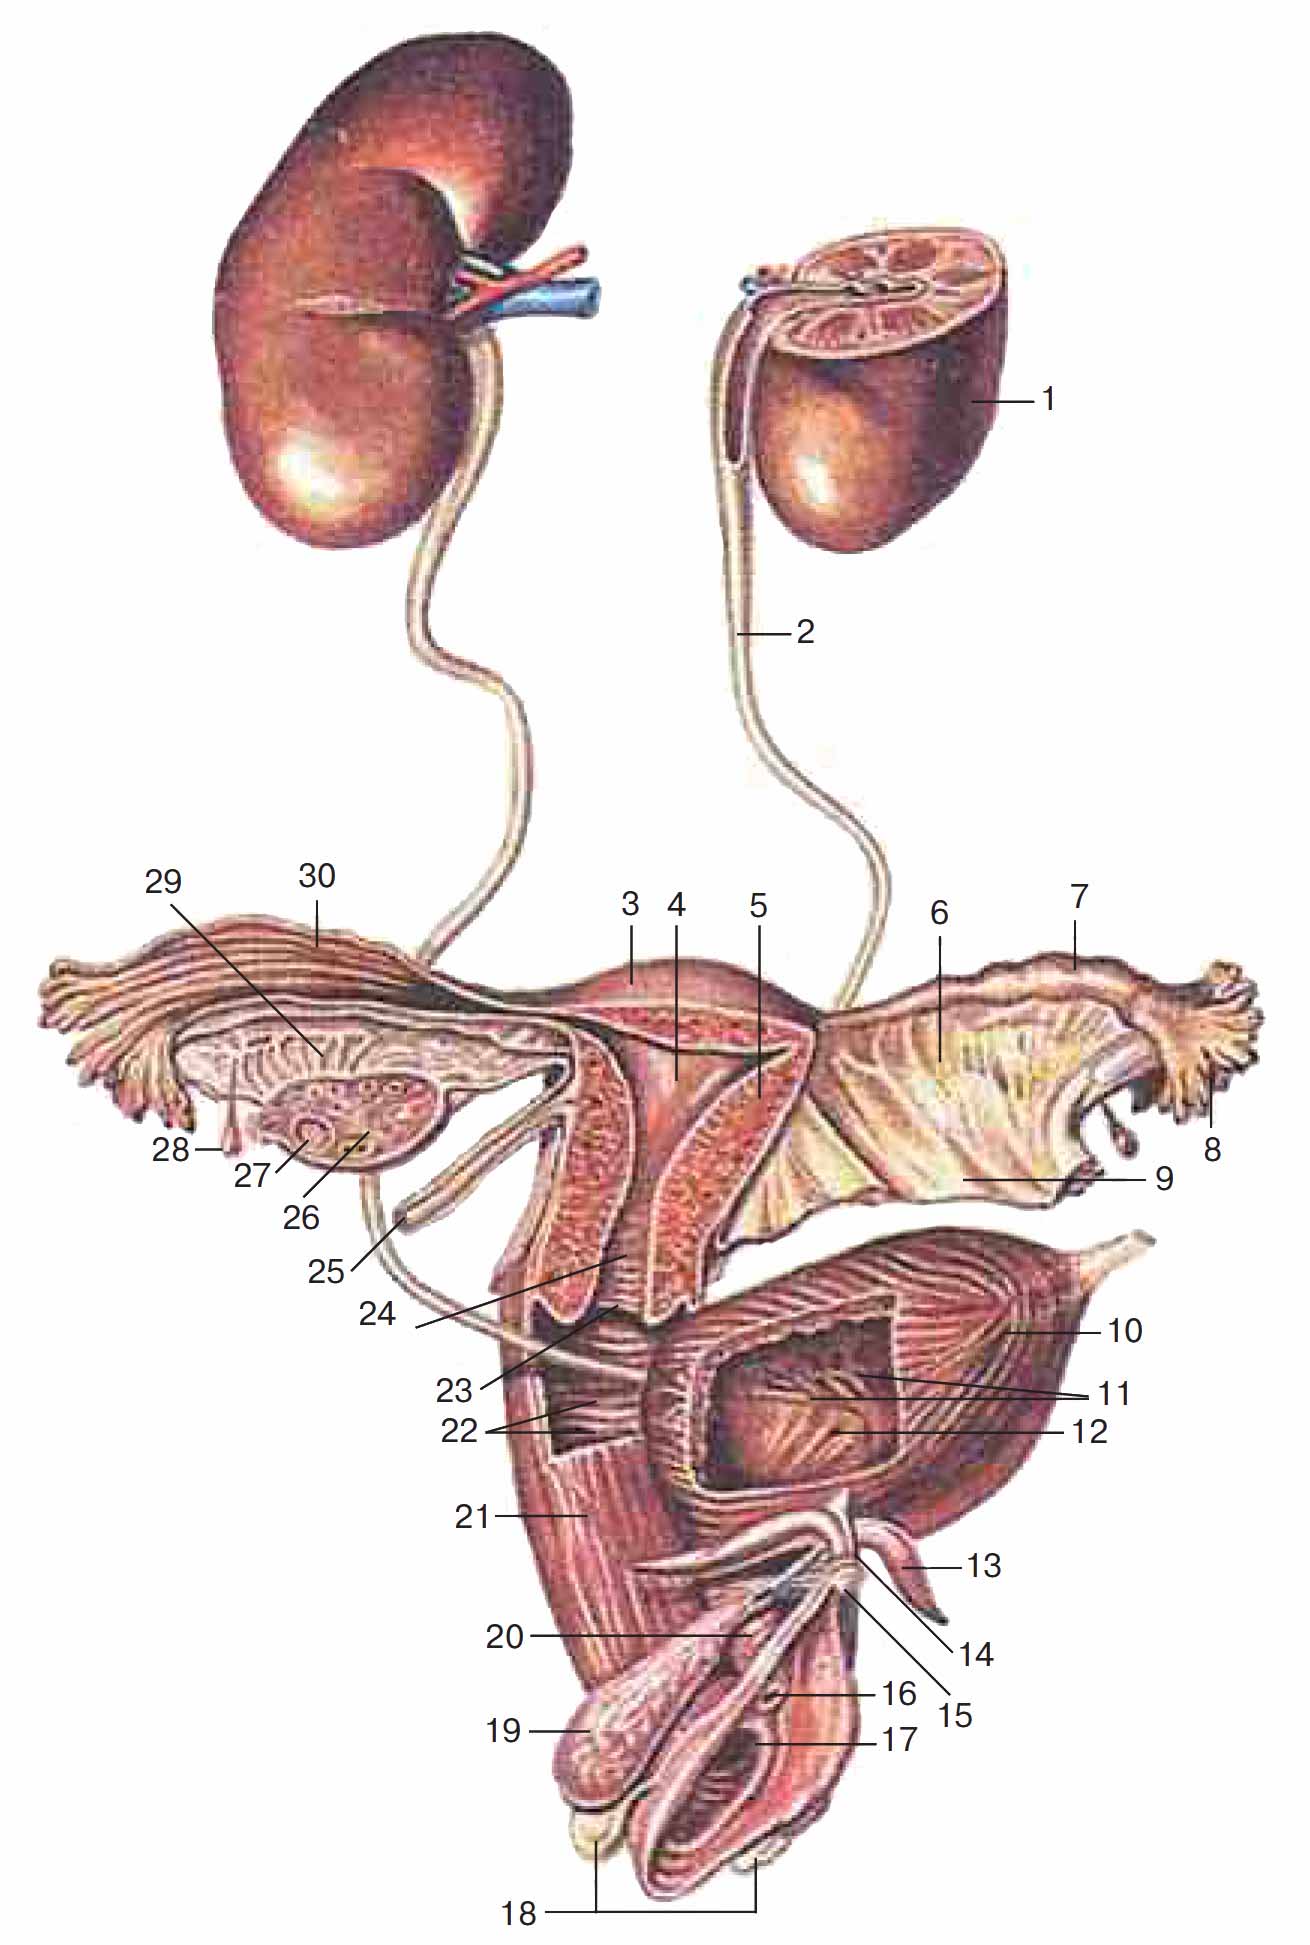

Интраренальная лоханка: рентгеновские снимки и примеры

Раздел: Фотоэссе